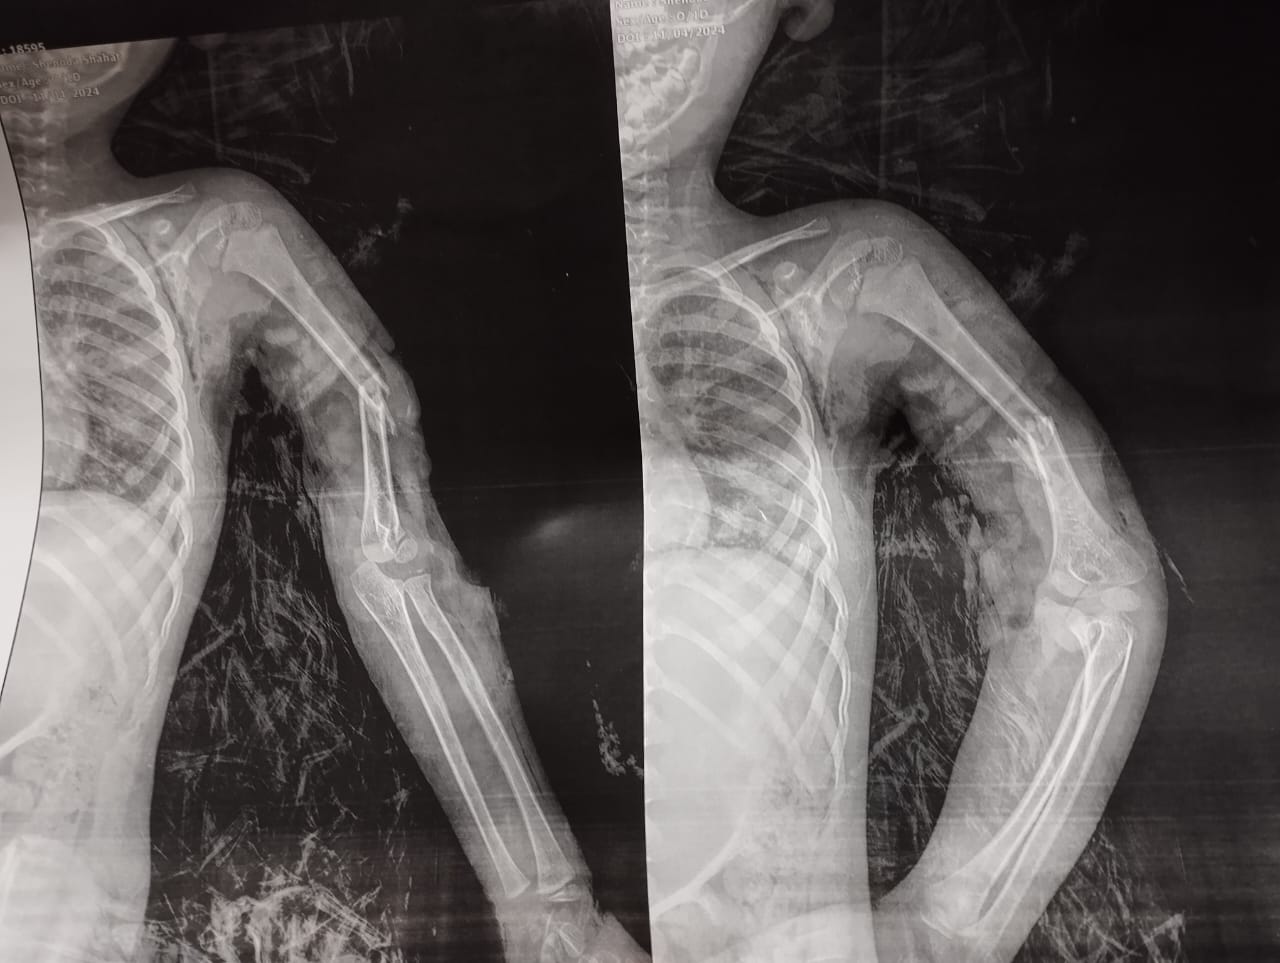

وقال الدكتور مجدي القاضي عميد كلية الطب البشري جامعة سوهاج، إن الطفل المصاب وصل إلى المستشفى في حالة حرجة جدًا بعد تعرضه لإصابة مباشرة من ماتور ري زراعي، وبتوقيع الكشف الطبي عليه من قبل أطباء الاستقبال والطوارئ بمستشفى جامعة سوهاج، فقد تبين وجود قطع في الأعصاب والشرايين المغذية للطرف العلوي الأيسر مع تهتك بالأنسجة وكسر بعظمة العضد اليسري.

ومن جانبه أكد الدكتور عبدالرحمن الشيخ رئيس قسم العظام، أنه على الفور تم التعامل مع الحالة وتم تثبيت الكسر بواسطة مسمار نخاعي مرن وتم توصيل الشرايين المغذية للطرف العلوي مع أخد رقعة وريدية من الطرف السفلي، مبينًا أن الحالة الآن بصحة جيدة وفي طور التحسن مع رجوع الدورة الدموية للطرف العلوي.